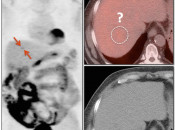

- Particularly useful in identifying very subtle liver lesions that may be missed on the axial images. [Case 2] [Case 3] [Case 4]

Axial Fused 103 – subtle FDG lesion right liver! - Case 705: 1 subtle lesion.

Quick MIP

Axial CT 117 – nothing seen

Axial Fused 117 – extremely subtle lesion? Only Quick MIP lets you notice it! - Case 103: Adenopathy not easily noticed, if not very hot.